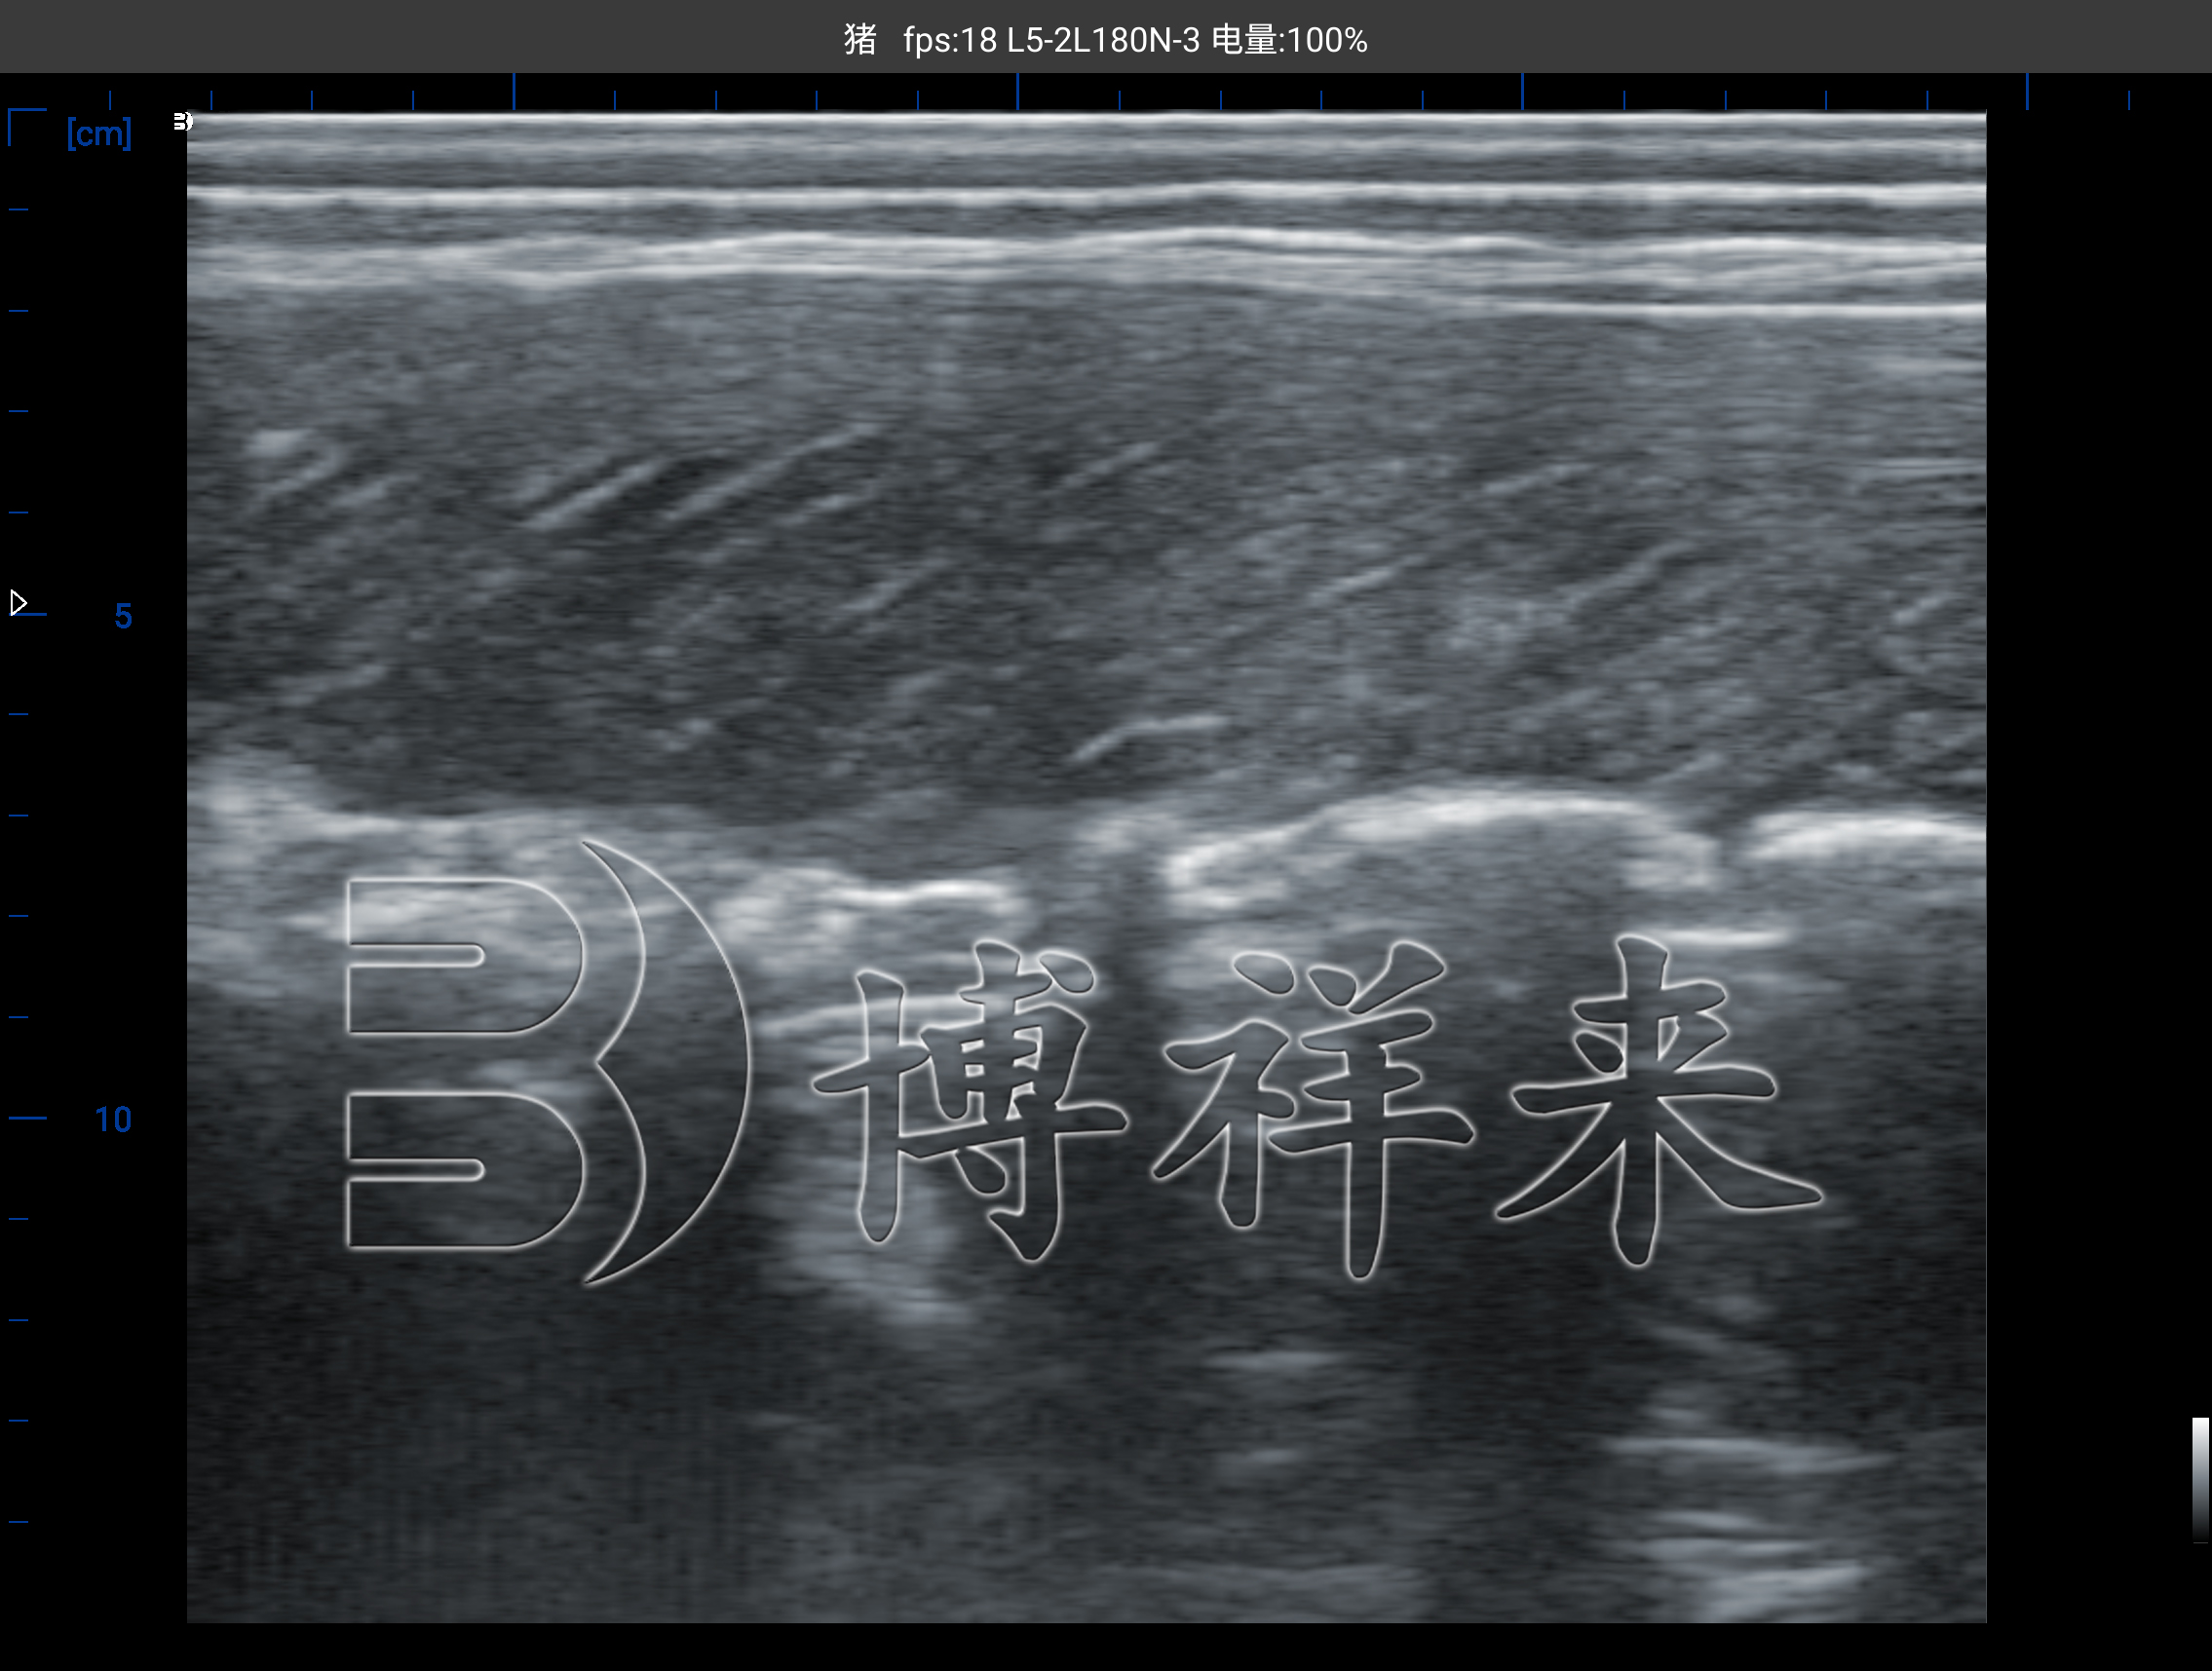

在传统育种管理中,选种往往依赖人工观察和体型估计,这种方式主观性强,误差较大。而智能背膘仪通过B超图像直接呈现背膘与眼肌结构,让育种决策从“凭感觉”变为“看数据”。

通过对猪体第10肋处进行检测,仪器可清晰显示:

背膘层的厚度与均匀性;

眼肌面积与形态;

肌肉与脂肪的比例结构。